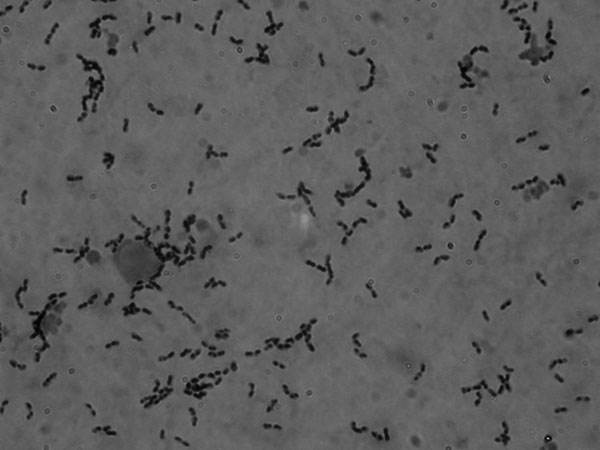

猪链球菌病主要表现为猪的败血性和局灶性淋巴结化脓性病症,猪链球菌的自然感染部位是猪的上呼吸道、生殖道和消化道。各种年龄的猪都会感染该病毒,但是败血症型和脑膜炎型常见于仔猪,化脓性淋巴结炎型多见于中猪。很多健康的猪群引入了带菌猪之后,由于互相接触,病菌可以通过口、鼻、皮肤伤口而感染。